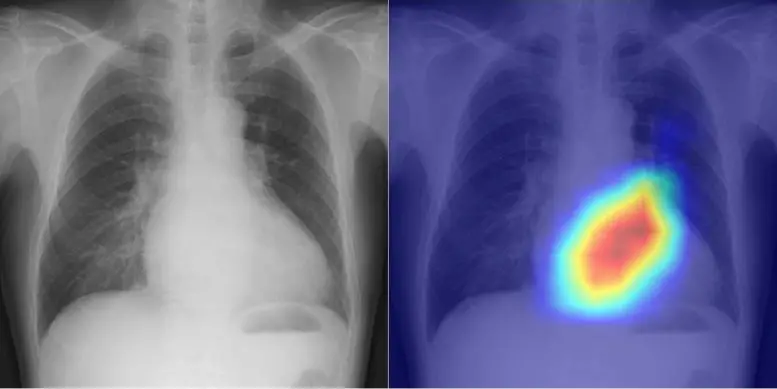

左:胸片 右: 人工智能判断依据的可视化。图片来源:OMU,上田大寿

上田博士的团队成功开发出一种利用人工智能的模型,可以从胸片上准确地对心脏功能和瓣膜性心脏病进行分类。由于在单一数据集上训练的人工智能可能会出现偏差导致准确率较低,因此该团队将目标放在了多机构数据上。因此,在2013年至2021年期间,研究小组从四家机构的16946名患者中收集了与22551张超声心动图相关的共22551张胸部X光片。将胸片作为输入数据,将超声心动图作为输出数据,对人工智能模型进行了训练,以学习连接这两个数据集的特征。

人工智能模型能够精确地对六种选定的瓣膜性心脏病类型进行分类,其曲线下面积(Area Under the Curve,简称 AUC)在 0.83 到 0.92 之间。(AUC是表示人工智能模型能力的评级指标,其数值范围为0至1,越接近1越好)。在检测左心室射血分数(监测心脏功能的一项重要指标)的 40% 临界值时,AUC 为 0.92。